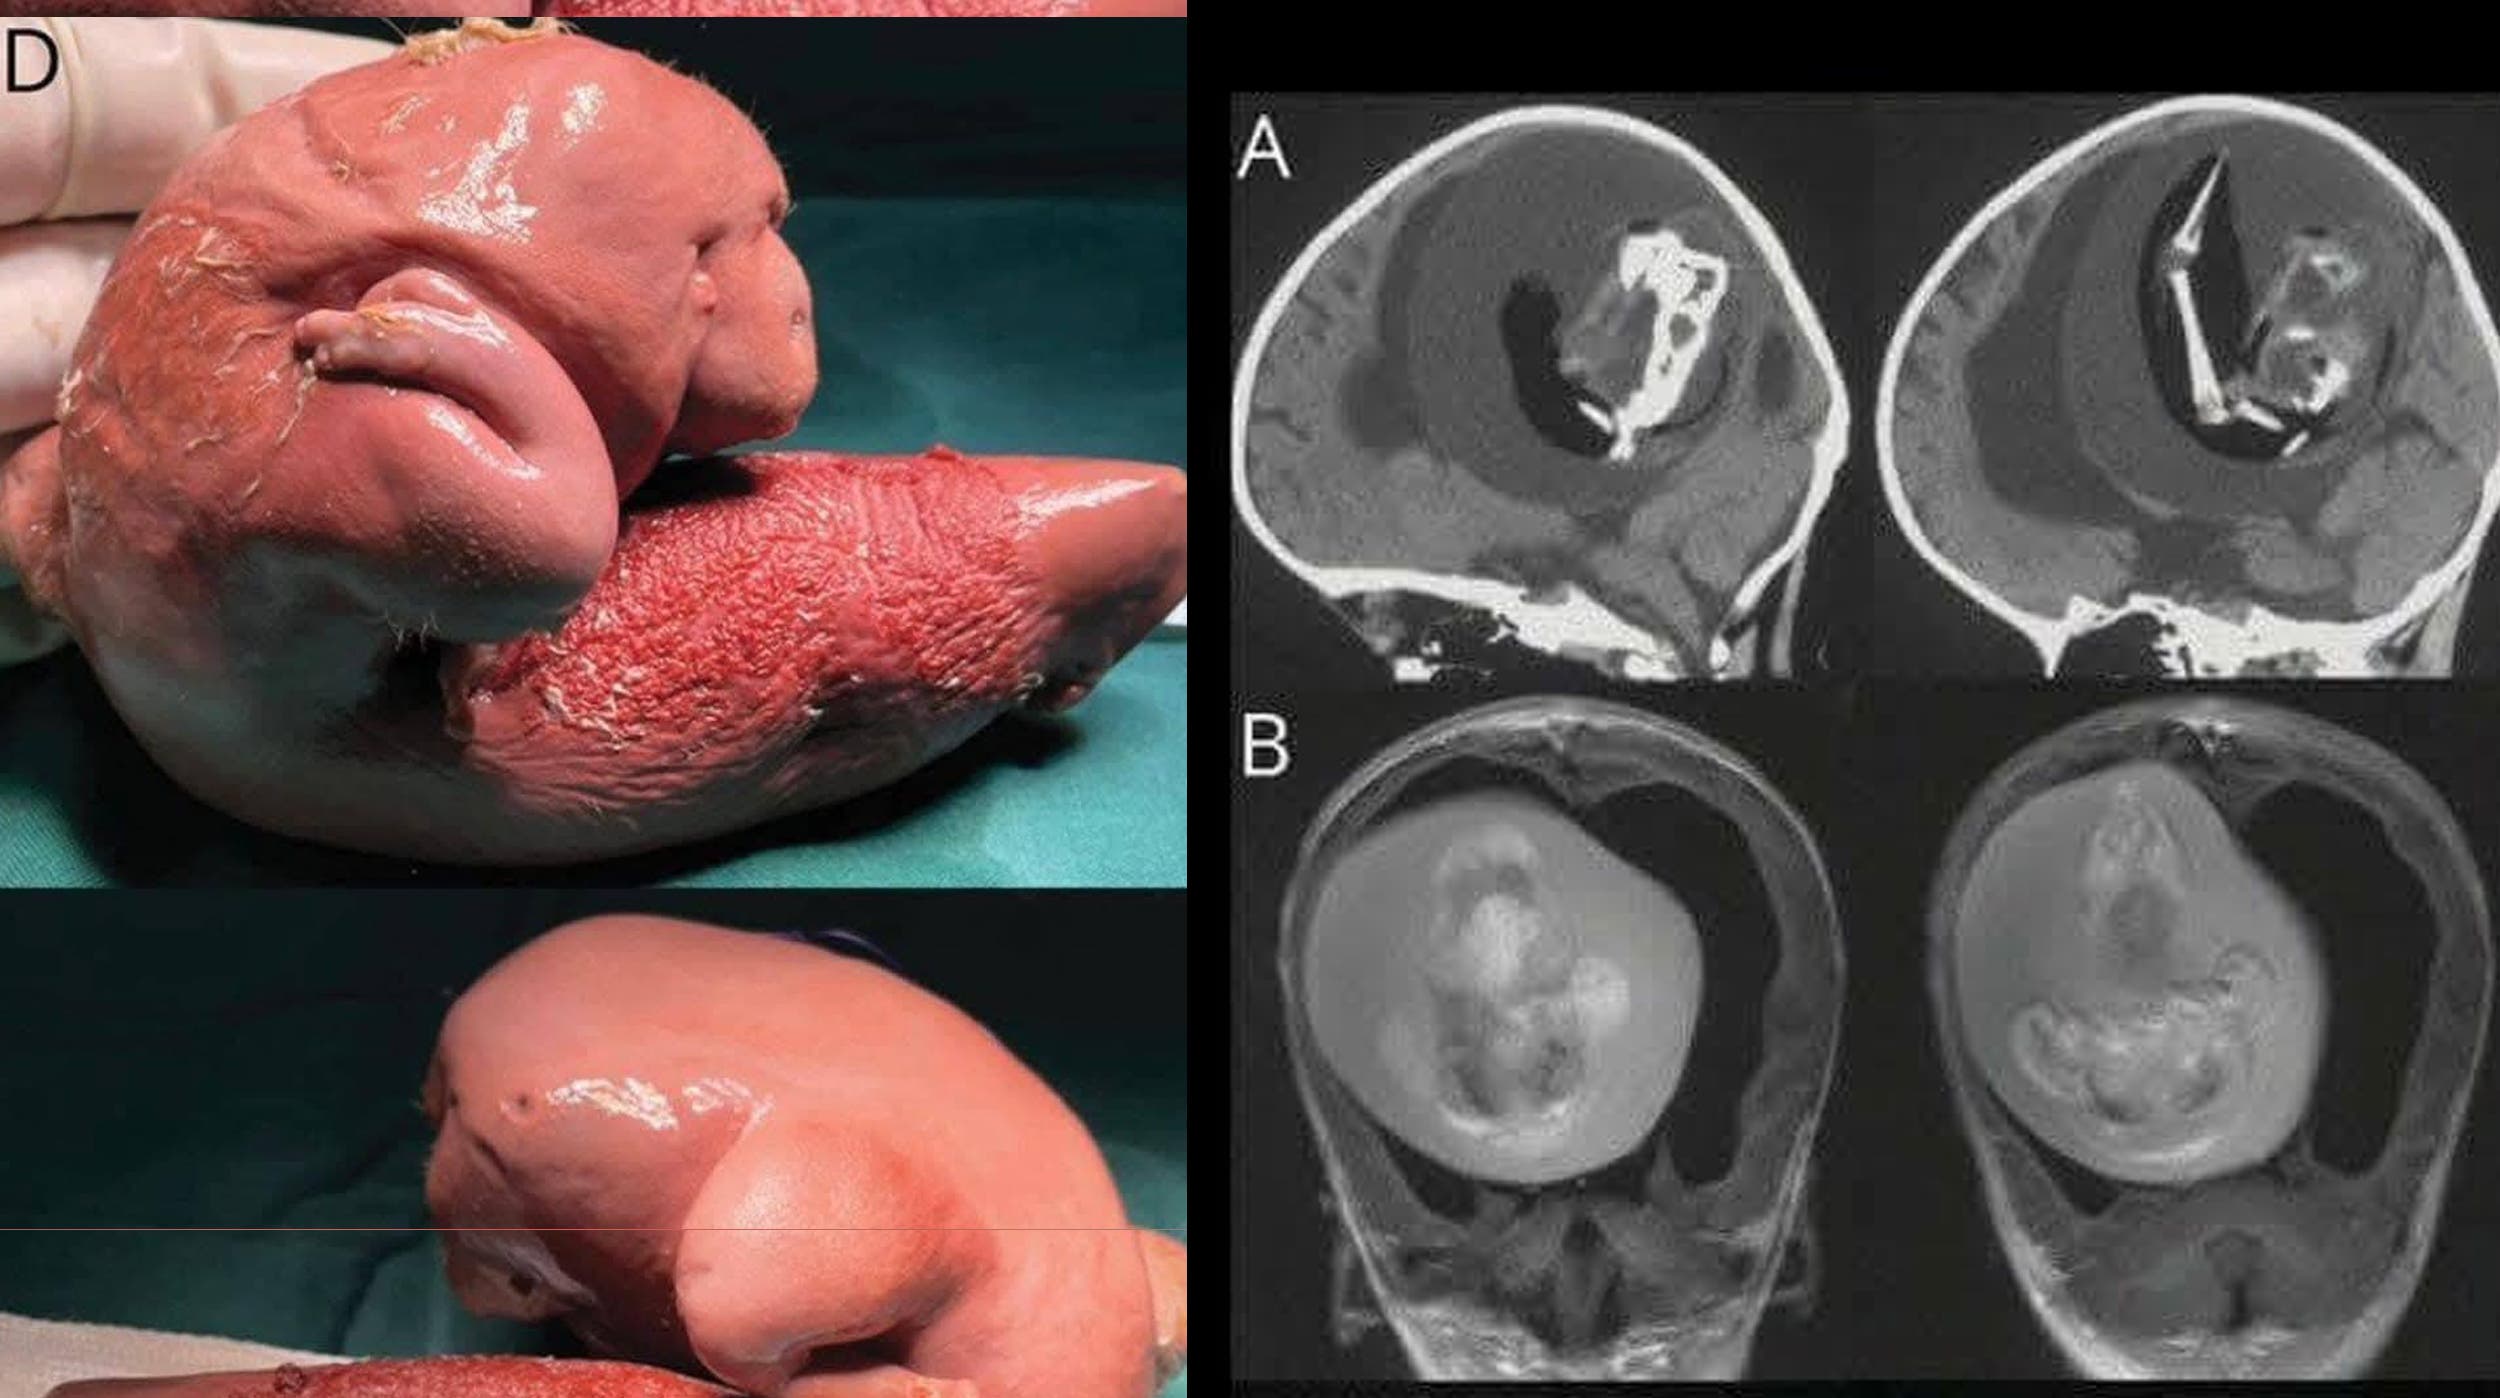

Un impactante y raro hallazgo médico ha dado la vuelta al mundo: una niña de apenas un año fue diagnosticada con un "fetus in fetu", una extraña condición en la que un gemelo malformado queda atrapado dentro del cuerpo de su hermano durante el embarazo. En este caso, los médicos descubrieron al “gemelo” alojado nada menos que en el cerebro de la menor.

El hallazgo se dio durante una serie de estudios rutinarios, cuando los médicos notaron una masa inusual en el cráneo de la pequeña. Tras realizar exámenes más avanzados, confirmaron la presencia del gemelo malformado, con estructuras bien formadas como huesos y tejidos. La niña fue atendida de inmediato y su evolución está siendo monitoreada por especialistas.

Fue descrito por primera vez en 1809, en la mayoría de los casos, la masa es no funcional, pero puede contener huesos, cabello o incluso órganos rudimentarios.